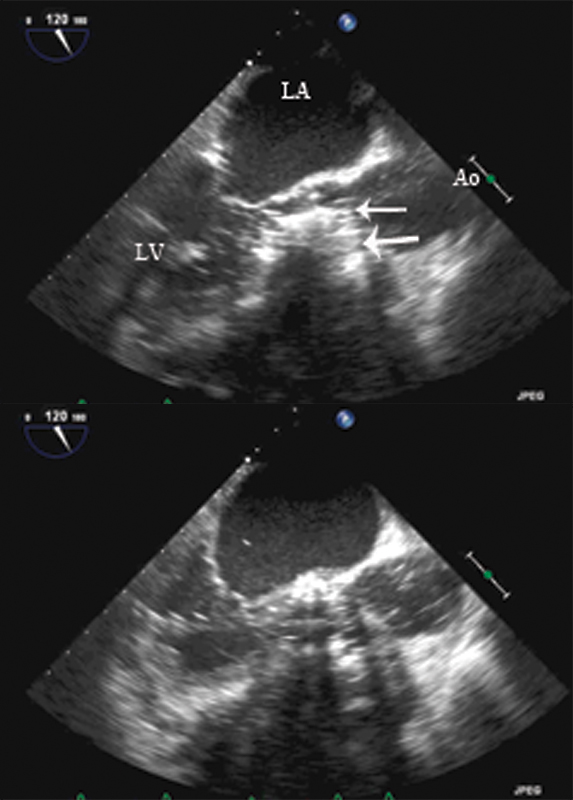

فحوصات تشخيصية لبعض امراض القلب والشرايين التاجية